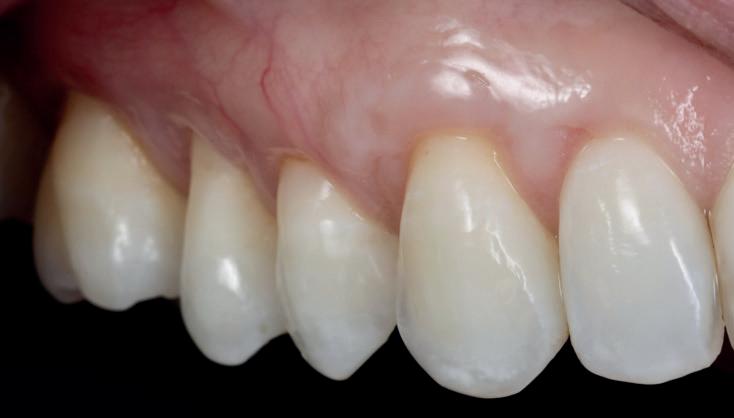

1 SHADE

2

This innovative owable composite transforms shade matching into an effortless process—no shade guide required. With just two complementary shades, U and UD, it seamlessly blends with the surrounding tooth structure. Its easy polishability and long-lasting high gloss enables you to create beautiful, natural-looking restorations with minimal effort. And with strength comparable to many paste-type composites, it’s suitable for a wide range of clinical applications.

FLOWABILITIES

Low and Super Low for a wide range of indications 150 IMPRESSIVE STRENGTH

Sufficient for use even in stressbearing posterior restorations

Covers all VITA* shades in all cavities, except those lacking of a back wall of shade B3 and darker